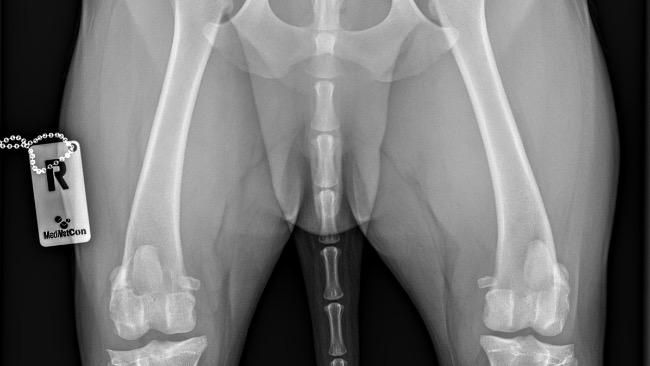

Został nam ponad miesiąc do kontrolnego zdjęcia RTG 🐾 okaże się czy wszystko zagoiło się tak jak powinno. Zeszliśmy z antybiotyku, pozostały tabletki przypisane przez lekarza na stawy. Dziękuję za każdą pomoc 🤎🐾

Jestem właścicielką cudownego czekoladka. Niestety po jednym ze spacerów nasz Labek zaczął kuleć. Wizyta u weterynarza potwierdziła, że musimy pilnie przeprowadzić operację zerwanego więzadła prawej łapy tylniej. Koszt takiej operacji łącznie to ok 5 tysięcy… kwota ogromna.Nasz Louis będzie bardzo wdzięczny za każde udostępnienie i wpłacona złotówkę. Im szybciej uda nam się zebrać potrzebną kwotę tym szybciej będzie mógł znów cieszyć się spacerami bez chodzenia na krótkiej smyczy. Jest to kwota potrzebna na operację (leki, znieczulenie, wizyty kontrolne i rehabilitacja).